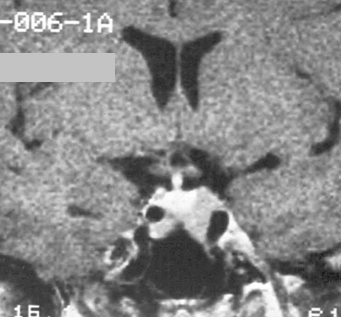

In the anterior lobe of the gland adenomas derive from the glandular structure. They can be grouped according to their hormone producing status:

hormonally active

hormonally inactive

According to their size they can be:

microadenomas (< 1 cm)

macroadenomas (> 1 cm)

Signal change on MRI in pituitary adenomas:

Microadenomas on T1WIs appear with much lower signal intensity compared to white matter, while compared to the grey matter they are only less intense.

On T2 weighted images they show great variability. They can be bright, isointense and hypointense as well.

Macroadenomas can show necrobiotic phenomena, thus due to hemorrhage and cystic degeneration their signal is inhomogeneous, especially on T2 weighted sequences. However homogenous macroadenomas can also be seen.